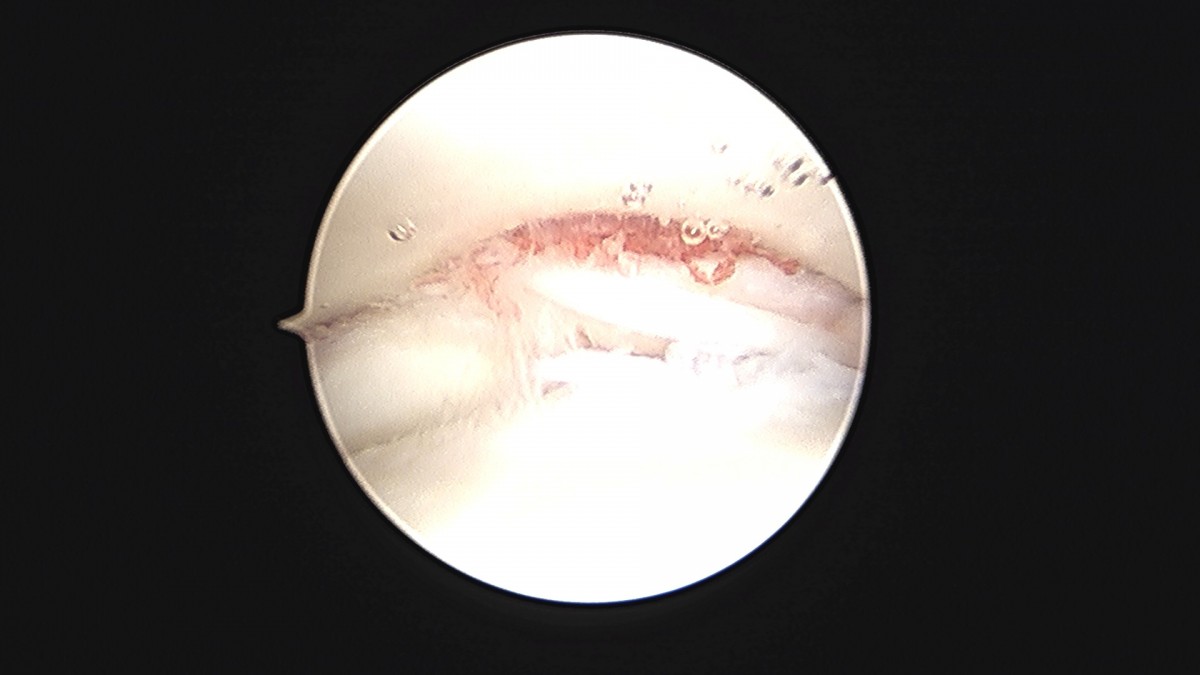

이재상원장님 발목 연골병변 제거술 및 골수 자극술 장경O 환자

dae765e4d9ac96aee867c9d6292d8784_1758006812_5262.jpg